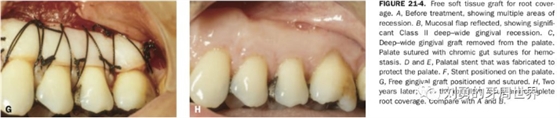

對于需要進(jìn)行根面覆蓋的手術(shù),移植瓣需要縫合固定到CEJ冠向1mm左右的位置。如下圖:

原因是:附著齦增寬的手術(shù),受區(qū)骨膜面積大,血供好,因此用偏薄的就可以,而對于根面覆蓋的手術(shù),受區(qū)外露根面沒有骨膜,血供差,因此取厚一點的,容易成活,對于牙槽嵴缺損的,建議取厚的,不是為了血供,而是為了更明顯的修復(fù)牙槽嵴的缺損。如下圖:

上面是附著齦增寬,因此取的薄一些。

上圖B23頰側(cè)牙槽嵴水平向塌陷明顯,為了增寬,取厚一點的齦瓣效果更好。